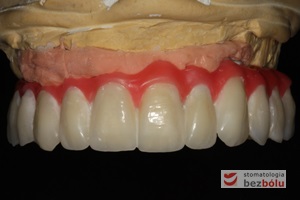

Gotowy most z maską dziąsłową - zastosowanie maski dziąsłowej uzasadnione długością zębów

Gotowy most z maską dziąsłową – zastosowanie maski dziąsłowej uzasadnione długością zębów